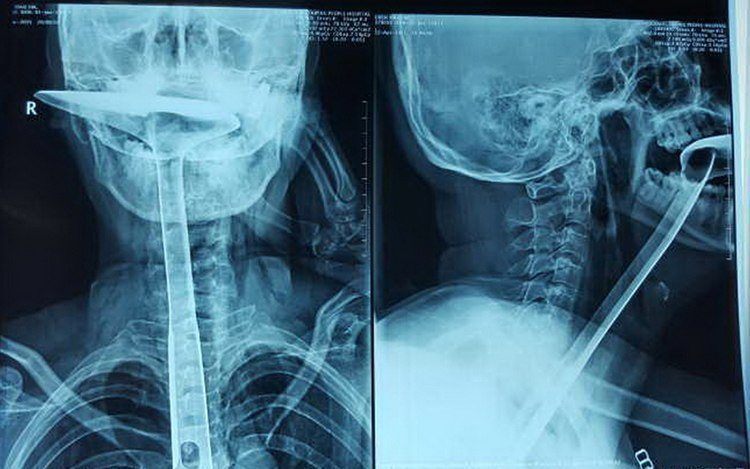

6. Pierced Through The Eye By A Leg Chair

This is a 3D X-ray photo. The subject of the photo - 20 year old Shafique el-Fahkri got into a fight when another man threw a chair right at him. As we can see the result was gruesome. One of the leg chairs pierced right through his eye sockets, right down into his neck.Advertisement